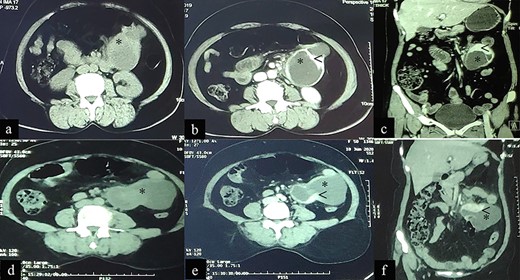

A 50-year-old female presented with a 2-year history of intermittent left flank pain occurring once every 1–2 months with each episode lasting for 6–7 days, which sometimes required analgesics. She also complained of gradually increasing anorexia, as well as abnormal stool consistency. The patient was previously seen at another facility 12-month earlier where a CECT of the abdomen showed a cystic lesion (8.98 × 5.34 cm) with enhancing wall, septa and a solid component (28 × 13 mm) in the left abdominal cavity abutting the jejunum anteriorly, psoas muscle posteromedially and the small bowel both superiorly and inferiorly, suggestive of an EGIST (Fig. 3 a–c). She initially opted for conservative treatment but her symptoms worsened and hence she visited to our outpatient clinic for further management.

Case 2: CT imaging of Extragastrointestinal stromal tumor. (a) Non-contrast axial; (b, c) contrast enhanced axial and coronal reformatted CT images of abdomen demonstrates intraperitoneal cystic lesion (*) with eccentric enhancing solid component (<) abutting kidney and bowel. (d) Non-contrast axial; (e, f) contrast enhanced axial and coronal reformatted CT images of abdomen of same patient after 1-year interval follow up demonstrates increased size of the lesion (*).

On presentation she was alert and oriented with no acute distress and normal vital signs. Her physical examination was unremarkable except for her abdominal findings, which revealed a soft, non-distended abdomen with a lower midline surgical scar, no striae, dilated veins, rashes or visible peristalsis. Bowel sounds and rectal exam were normal. A fixed mass (12 cm × 8 cm) was appreciated in the left-upper quadrant. A complete blood count, renal function test, liver function test and coagulation profile were all normal. Repeat CECT of the abdomen and pelvis showed an intraperitoneal cystic lesion (83 × 80 × 59 mm) with an eccentric enhancing solid component (73 × 29 mm) within the mesentery abutting an area from the distal duodenum to the jejunal loop inferiorly with features suggestive of an EGIST (Fig. 3d–f).